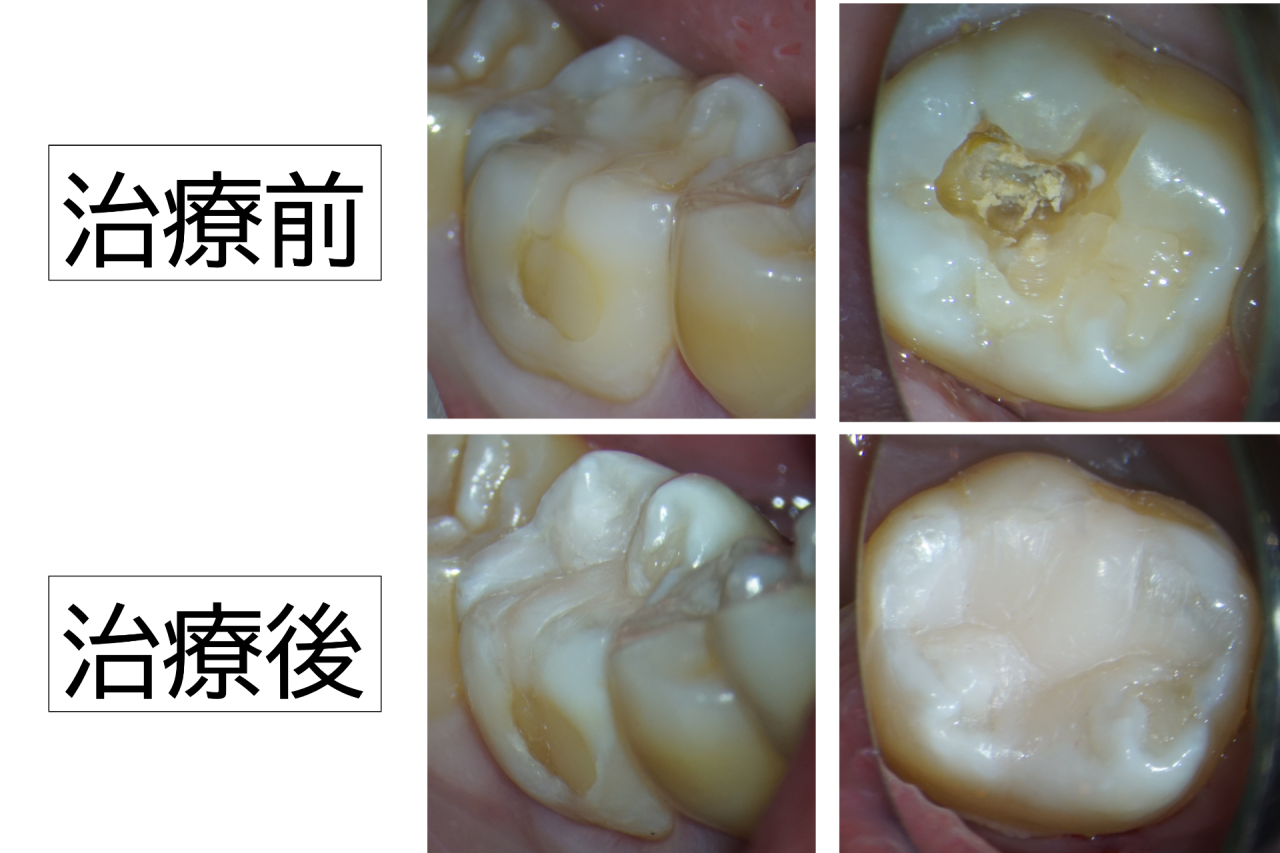

丁寧に時間をかけて削らない治療を

なるべく「歯を削らない」「神経を取らない」ことを念頭に、痛みの少ない治療を実施しております。特に、顕微鏡検査により虫歯の早期検査・早期発見を心がけ、皆様の歯の健康をお守りしています。丁寧に1本ずつ時間をかけて治療を行うことで、なるべく元の歯の形を残し、自然な状態に治すことを目指します。

「歯の治療はなるべくしたくない」「痛みの伴う治療は避けたい」と考える方は多いのではないでしょうか。まずは顕微鏡検査により、精度の高い状態で歯を確認し、削るべきか、神経を取るかなどを判断いたします。その中で、なるべく歯を削る負担をおかけしないよう、小さく削り、自然な状態に治すよう励んでおります。虫歯の進行状況により治療方法や通う回数も異なりますので、事前にしっかりとご相談を重ねます。治療を行う上で、ご相談したいことや不安に思うことなど、懸念点をお話しいただければ嬉しい限りです。